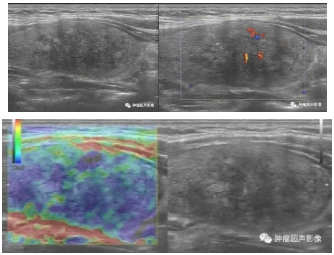

右侧颈部疼痛,右侧甲状腺肿大,形态不规则的低回声,边界模糊不清,回声不均匀,病灶回声从外向内逐渐降低,CDFI血流稀少;弹性成像显示质硬。